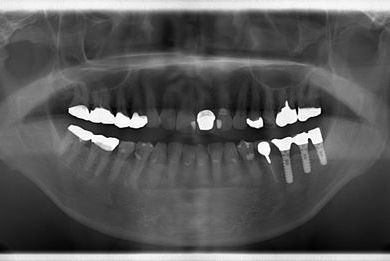

| 性別/年齢 | 男性 / 69歳 | ||||||||||||||||||||||||||||||||

| 主訴 | 1.左上奥歯の詰め物が取れた 2.左上前歯の欠け 3.右下奥歯の欠け | ||||||||||||||||||||||||||||||||

| 治療方針 | セラミック治療にて、審美的回復を行う。 | ||||||||||||||||||||||||||||||||

| 治療内容 | メタルボンドセラミッククラウン1本(メタルボンド用土台1本)、ハイブリッドセラミックインレー1本 | ||||||||||||||||||||||||||||||||